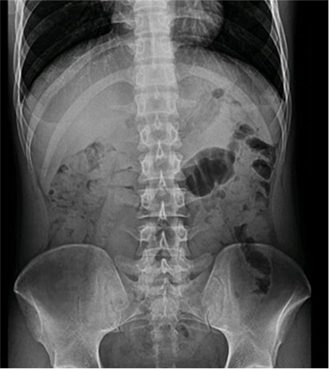

臨床圖片

微信圖片_20210927001116